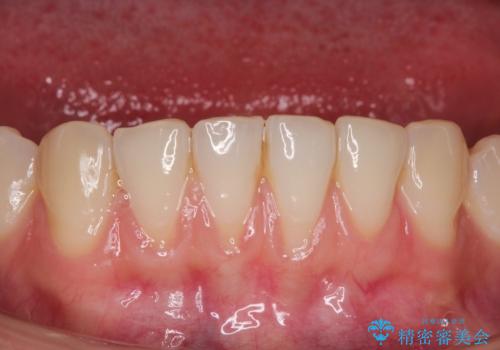

【オールセラミック】下の前歯が痛い。

- 以前に治療した前歯が痛むことを主訴に来院されました。

根っこに病気があり、根管治療から被せ物まで治療を行いました。

根管治療を行った後、3ヶ月間治癒の確認をしてからオールセラミックスペシャルで治療を行いました。